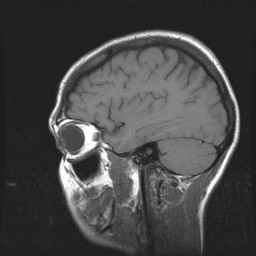

Schedel